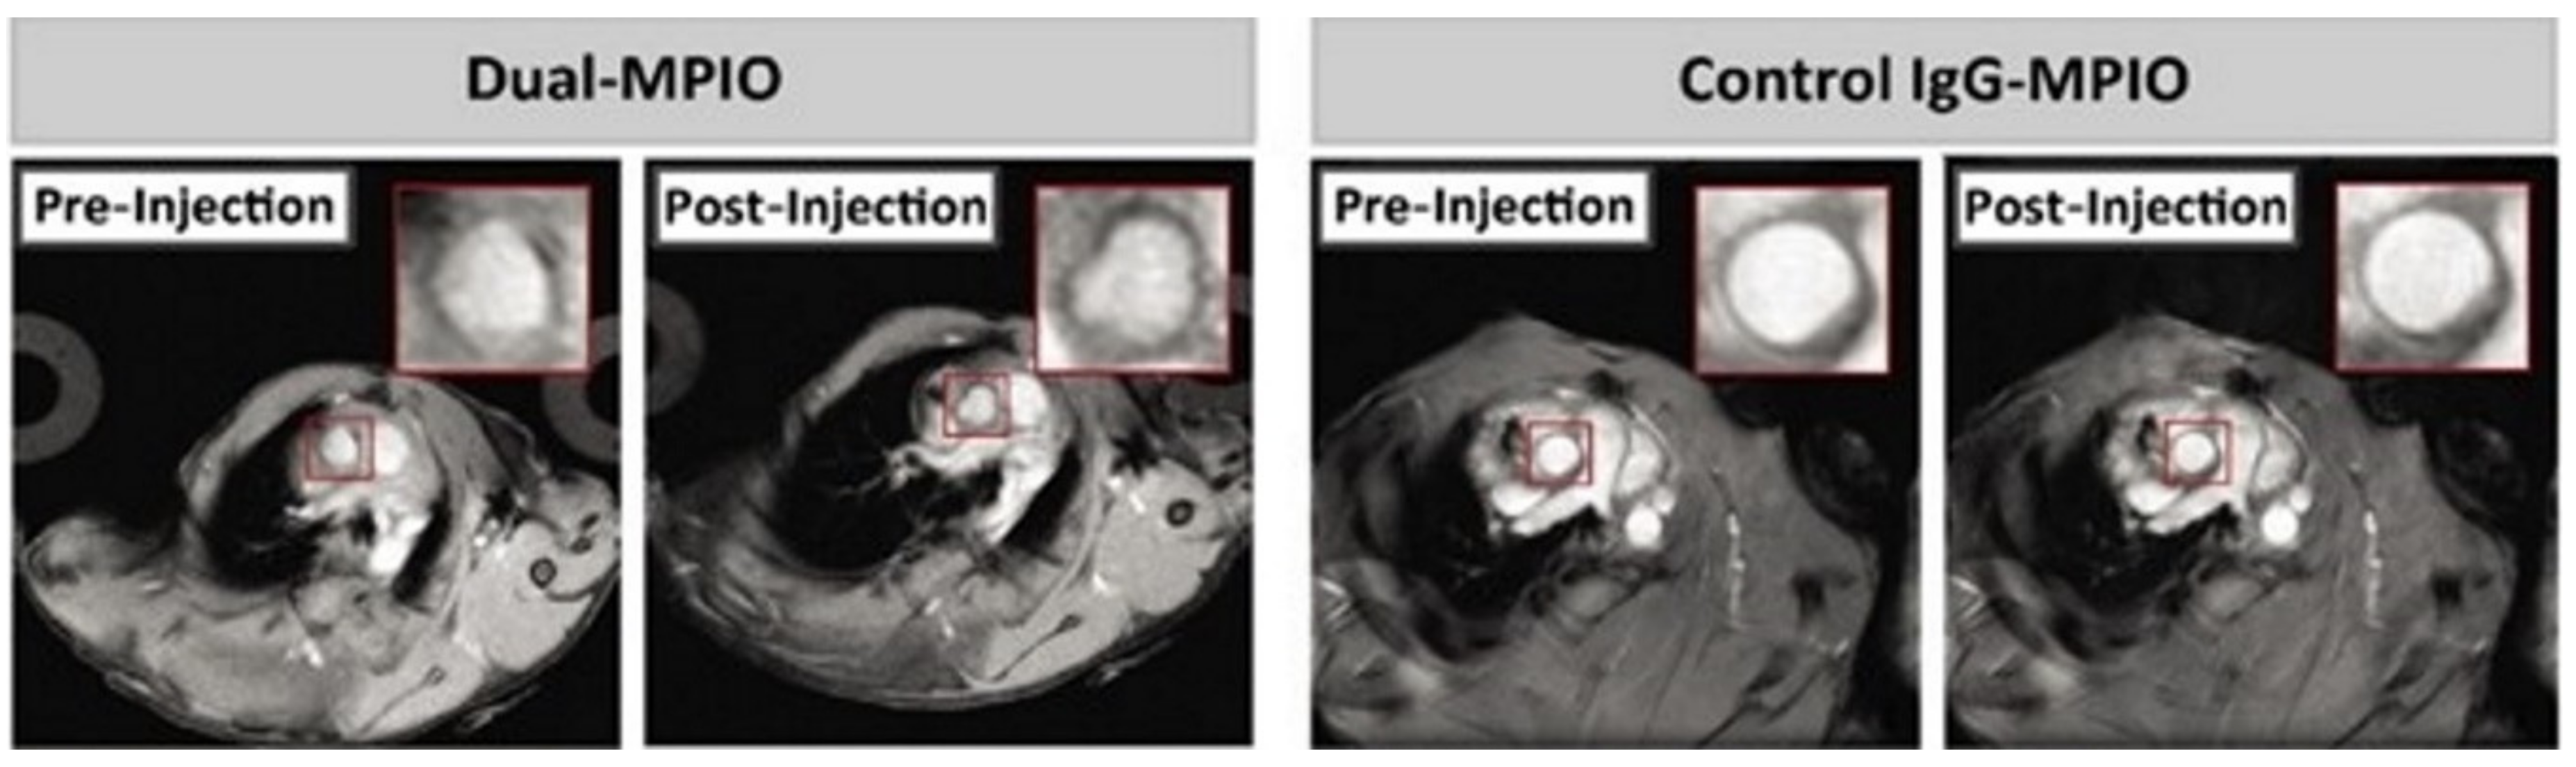

- Chan, J.M.S.; Monaco, C.; Wylezinska-Arridge, M.; Tremoleda, J.L.; Cole, J.E.; Goddard, M.; Cheung, M.S.H.; Bhakoo, K.K.; Gibbs, R.G.J. Imaging Vulnerable Plaques by Targeting Inflammation in Atherosclerosis Using Fluorescent-Labeled Dual-Ligand Microparticles of Iron Oxide and Magnetic Resonance Imaging. J. Vasc. Surg. 2018, 67, 1571–1583. [Google Scholar] [CrossRef]

- McAteer, M.A.; Schneider, J.E.; Ali, Z.A.; Warrick, N.; Bursill, C.A.; Von Zur Muhlen, C.; Greaves, D.R.; Neubauer, S.; Channon, K.M.; Choudhury, R.P. Magnetic Resonance Imaging of Endothelial Adhesion Molecules in Mouse Atherosclerosis Using Dual-Targeted Microparticles of Iron Oxide. Arterioscler. Thromb. Vasc. Biol. 2008, 28, 77–83. [Google Scholar] [CrossRef]